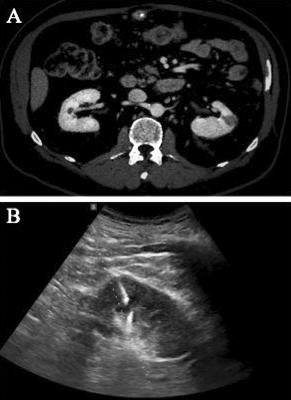

taining the autonomic nerves that reach the proximal sphincter The superior and inferior bladder arteries were dissected at their origin, at the level of the hypogastric arteries, while the uterine arteries and vaginal branches to the paravaginal tissues were spared Once the retropubic space was created and opened, the endopelvic fascia was incised very close to the bladder neck to reduce the risk of inadvertent injury to the paraurethral neurovascular structures, which are crucial for sexual function and continence (Figures 1, 2) The urethra was carefully prepared, exposed and divided, and a specimen was sent for extemporaneous histopathological examination (Figure 3) At this time, careful dissection of the retroperitoneal lymph nodes was performed The margins of the resection were cranially defined by the common iliac artery,

Cisternino, L Capone, A Rosati, C Latiano, N Sebastio, A Colella, G Cretì Figure 1. Development of the plane between uterus and bladder Figure 2. Genital sparing cystectomy with sparing of the uterus, ovaries, tubes and vagina